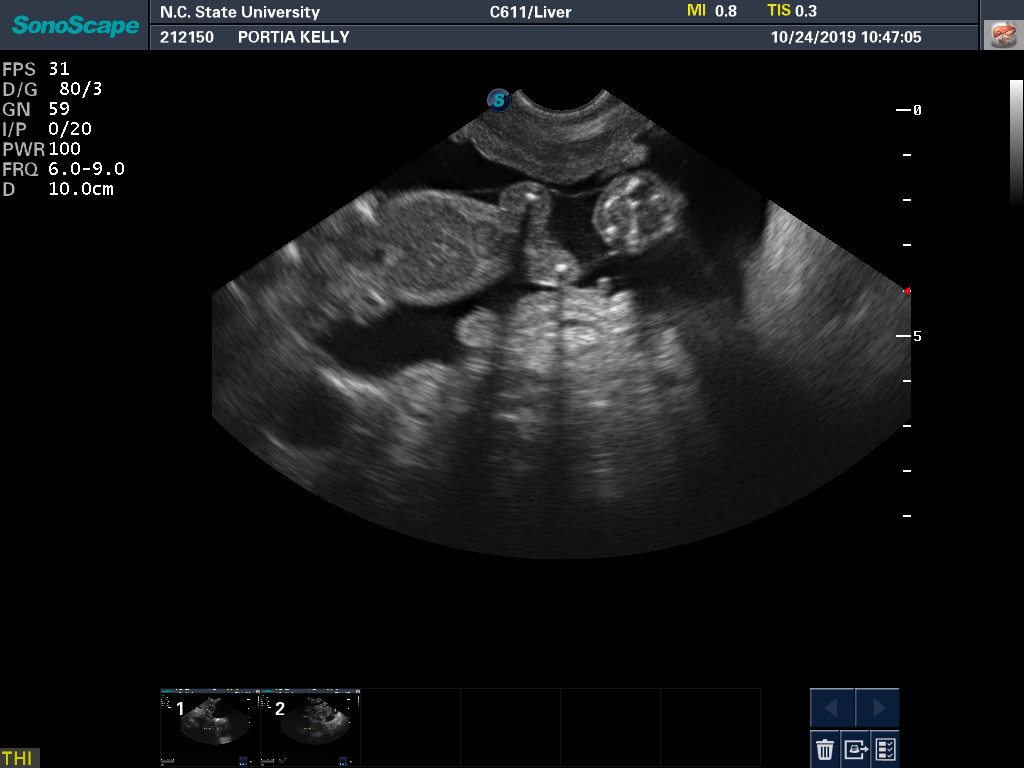

24 Oct

Portia's ultrasound today again showed healthy puppies. Blood was drawn to check Portia's progesterone levels. During a pregnancy, the progesterone level slowly drops. If the progesterone level gets too low too quickly, it can result in preemie puppies.

Here are two ultrasound pictures: